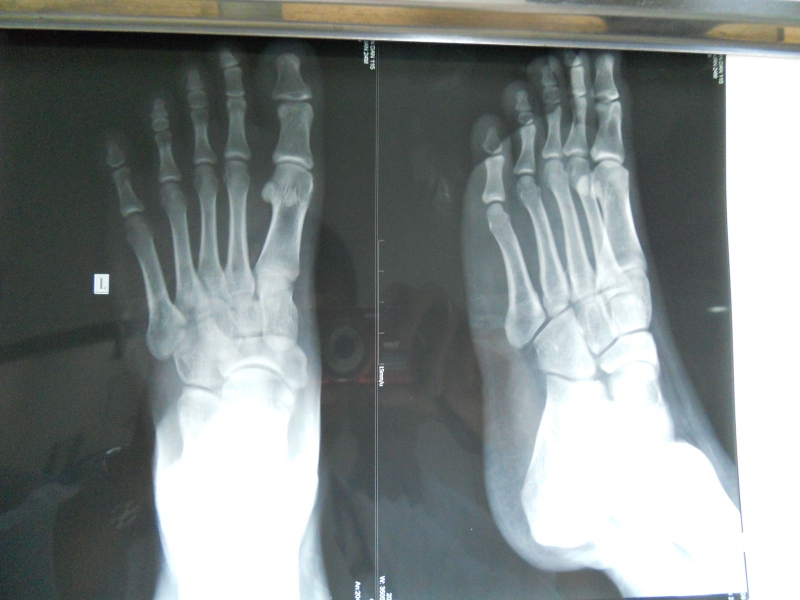

Ngoài các triệu chứng có thể nhìn thấy bằng mắt, bong gân ở bàn chân có thể được chẩn đoán bằng một số kỹ thuật thăm khám như Lachman test, test vẹo trong, test ngăn kéo trước, vẹo ngoài khớp… Bên cạnh đó, bác sĩ sẽ yêu cầu chụp thêm X-quang, CT, MRI bàn chân để có hình ảnh chi tiết tổn thương dù là nhỏ nhất hoặc loại trừ khả năng gãy xương.